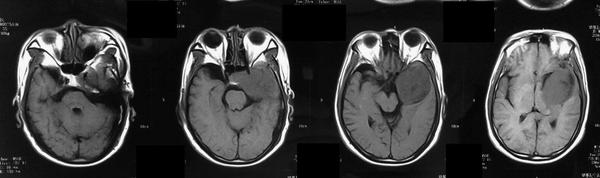

CT表现呈等密度、混杂密度、病灶边缘见小片高密度钙化。所有病灶边缘均光滑,与邻近脑实质分界清晰,无瘤周水肿,增强检查后均呈显著强化,强化均匀、部分不均匀,颈内动脉海绵窦段受压移位,部分病灶包绕血管,颈内动脉未见明显狭窄。CT骨窗上有中颅窝底、前床突及岩尖部等有骨质吸收,未见明显骨质增生。

MRI表现:病灶中相对脑实质来说T WI上呈等信号,或稍低信号,信号均匀,少数内部见小片高信号。T WI及T 一FLAIR上均为明显高信号。CSHAs的血供丰富及解剖结构较复杂,术前误诊率和术后致残率均较高,掌握其CT、MR及DSA等各种影像学检查方面的特征性表现,可提高术前定位及定性诊断的准确率,对于临床治疗方案的制定、确定手术入路以及减少手术致残及致死率有着十分重要的意义。